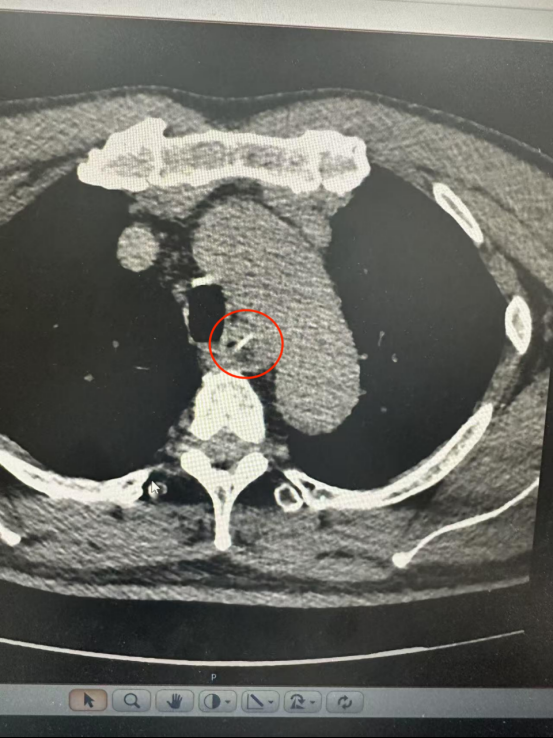

CT結(jié)果顯示一根長(zhǎng)約25毫米的魚(yú)骨卡在食管中段,兩端分別緊貼食管管壁外緣與主動(dòng)脈弓內(nèi)側(cè)。主動(dòng)脈是人體最粗大的動(dòng)脈血管,魚(yú)骨所處位置極為危險(xiǎn)。

根據(jù)CT三維重建結(jié)果,魚(yú)骨緊貼主動(dòng)脈弓但未刺破主動(dòng)脈及食管全層,尖端與主動(dòng)脈切線垂直,呈“一”字型排列。